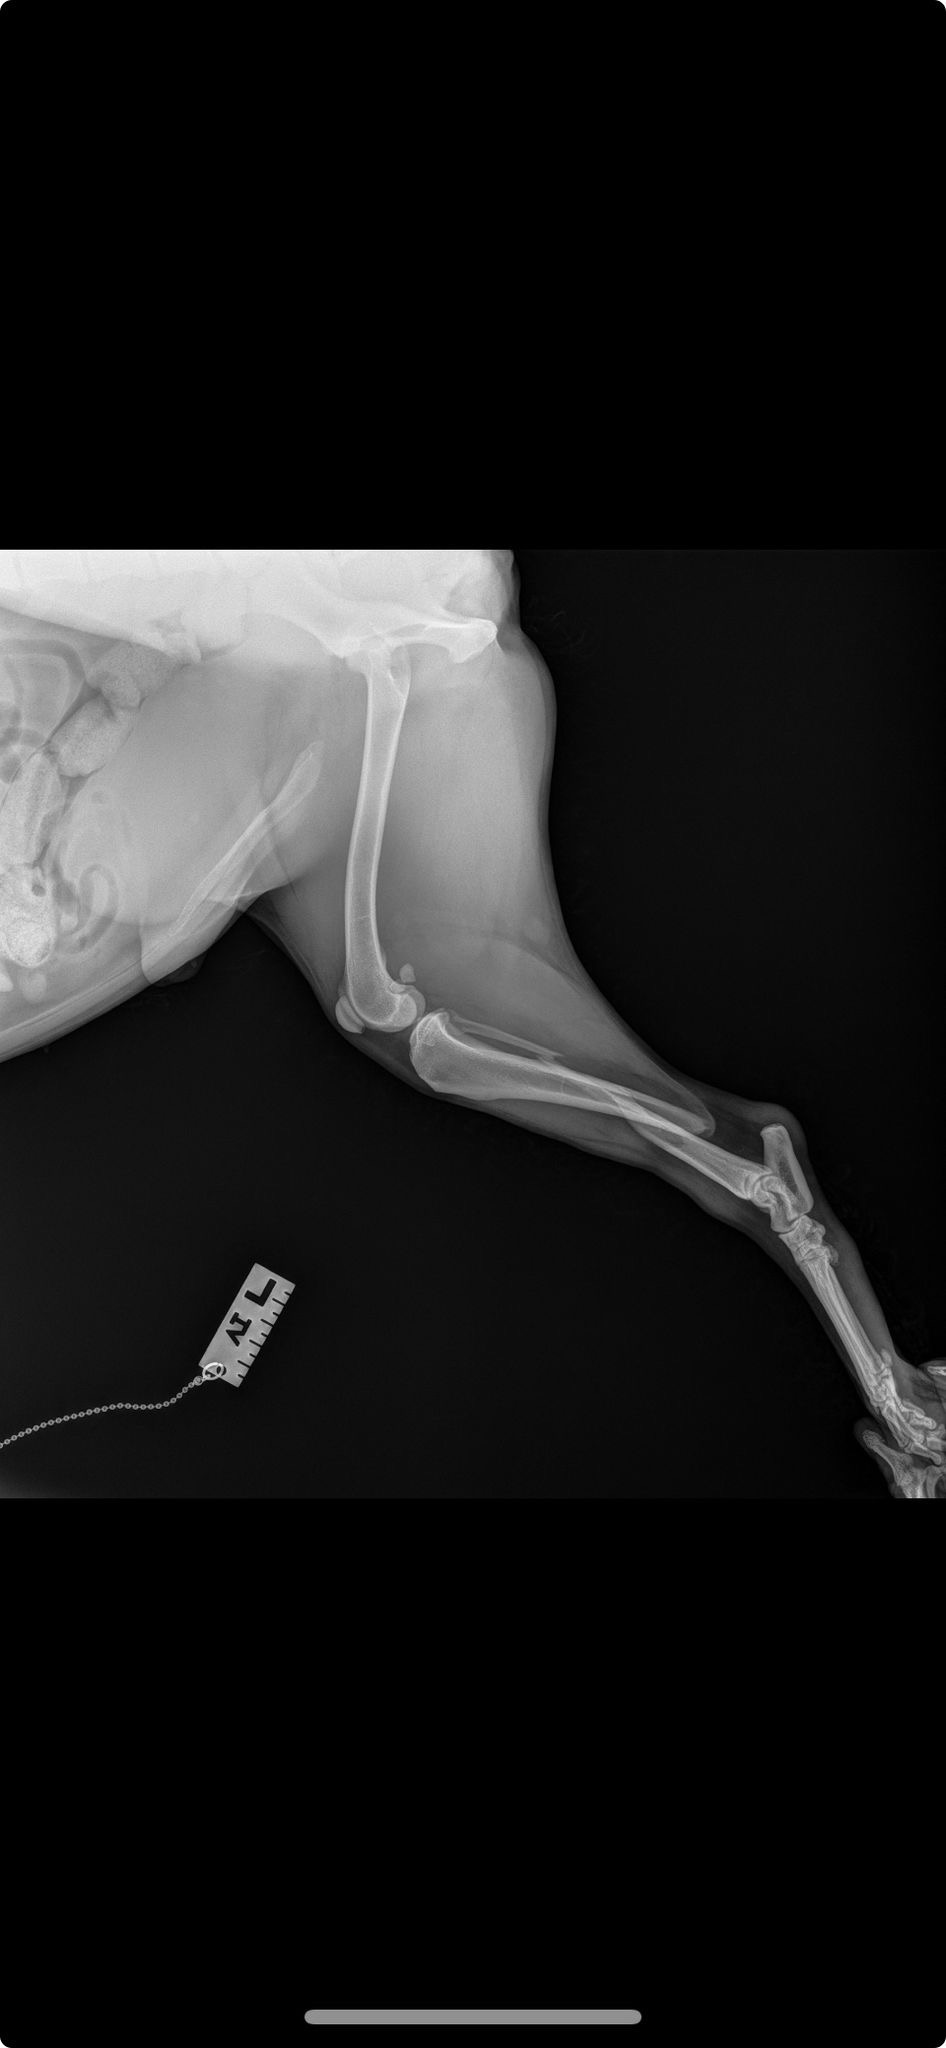

Help support kandy & Harry through medical emergency surgery. Leg surgery needed otherwise amputation